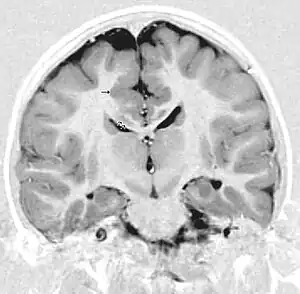

- Radiological findings (MRI) demonstrated symmetric generalized polymicrogyria with decreasing anterior-posterior gradient, most prominent in frontoparietal cortex.[5]

- Numerous gyrus on the cortex

- Small gyri and sulci

- Thin cortex

There are different tests or methods used to determine GPR56 expression or visuals of the brain to analyze the specific sections that are affected. These tests for example, using animals such as mice, RNAi, Behavioral assay, Electron microscopy, CT scan, or MRI demonstrate different results that concludes an affected BFPP patient.[16] MRI's reveal either irregularity to the cortical surface suggestive of multiple small folds or an irregular, scalloped appearance of the gray matter-white matter junction.

Neuroimaging The diagnosis of polymicrogyria is typically made by magnetic resonance imaging (MRI) since computed tomography (CT) and other imaging methods generally do not have high enough resolution or adequate contrast to identify the small folds that define the condition. The cerebral cortex often appears abnormally thick as well because the multiple small gyri are fused, infolded, and superimposed in appearance.[5]